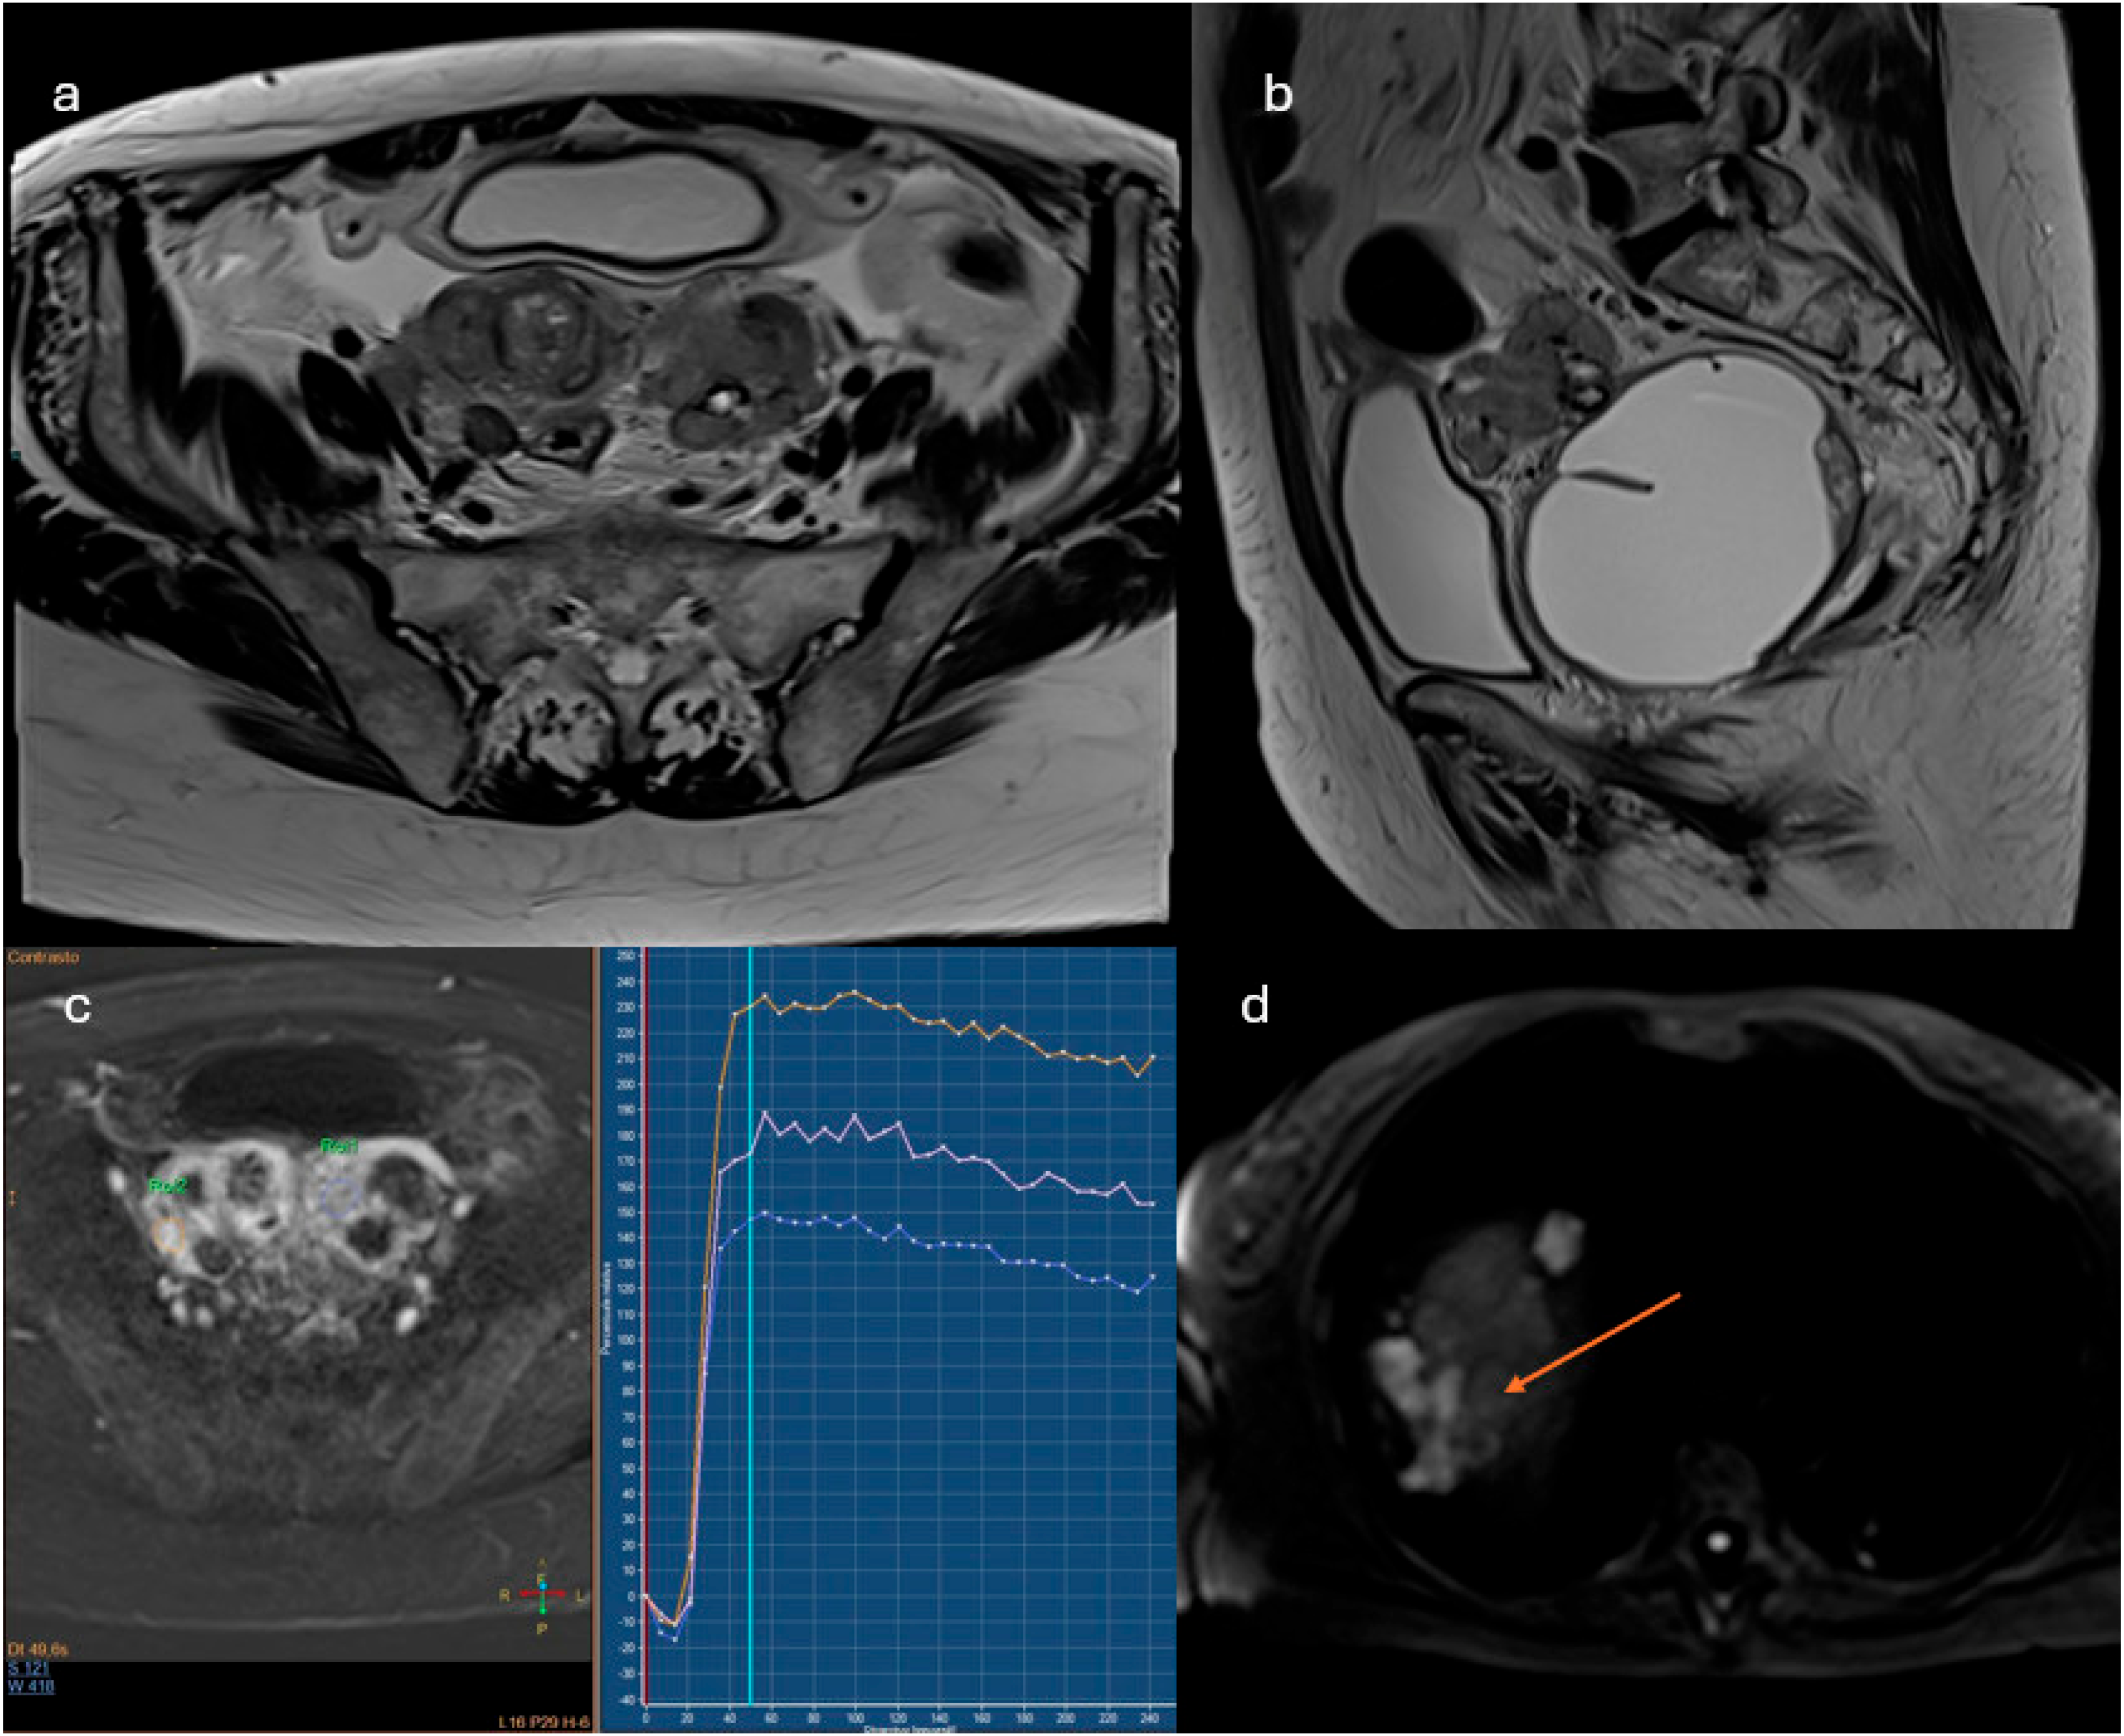

2.3.1. ADNEX-MR Scoring System

- Probably benign lesions: absence of solid tissue or solid tissue with type 1 enhancement curve

- Indeterminate lesions: presence of solid tissue with type 2 curve

- Likely malignant lesions: type 3 enhancement curve and presence of peritoneal implants

- Lesions with solid tissue (excluding solid lesions described in score 2) showing type 2 enhancement curve (intermediate risk; Figure 5)

- Lesions showing a type 3 enhancement curve (high risk)

- Solid lesions showing enhancement > myometrium at 30–40 s, if perfusion study is not available

- Lesions associated with the presence of peritoneal implants and/or secondary disease localization (Figure 6)